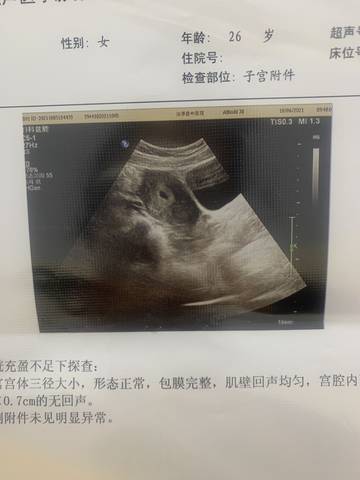

各位大神们 都来帮我看看这个孕囊是圆形还是长条形状,就是好奇,自己看不出来哦????

茄子吧, 有听说椭圆是女孩,茄子是男孩,但这个一般情况下是很难直接判断男孩还是女孩的,民间有个说法,肚子尖尖的是男孩,宝妈可以参考一下